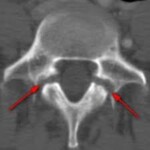

Ἡ σπονδυλολίσθηση εἶναι τὸ τίμημα, ποὺ ὁ ἄνθρωπος πληρώνει διὰ τὸ δῶρο τῆς δημιουργίας, ποὺ τοῦ ἐπιτρέπει νὰ στέκεται ὄρθιος στὸν δρόμο τῆς ζωῆς του. Πιθανώτατα εἶναι συνέπεια χρονίας λορδωτικῆς φορτίσεως, προκύπτει δὲ στὰ πλαίσια ἑνὸς κατάγματος ἐκ κοπώσεως, ποὺ καλεῖται σπονδυλόλυση καὶ δημιουργεῖται στὸν αὐχένα τοῦ σπονδυλικοῦ τόξου τοῦ Ο5 (90%) σπανιώτερα τοῦ Ο4 (εἰκ.7). Τότε λοιπὸν ἐπέρχεται σταδιακὰ ὀλίσθηση τοῦ σπονδύλου πρὸς τὰ πρόσω, ποὺ καλεῖται σπονδυλολίσθηση, ἡ πλήρης δὲ ὑπέρβαση τοῦ ὑποκειμένου σπονδύλου ὑπὸ τοῦ ὑπερκειμένου, καλεῖται σπονδυλόπτωση.

Ἡ διεθνὴς ταξινόμηση τῶν σταδίων τῆς σπονδυλολισθήσεως ἀκολουθεῖ τὸν ὑποδειχθέντα ὑπὸ τοῦ Meyerding κανόνα, σύμφωνα μὲ τὸν ὁποῖο τὸ μῆκος τῆς ὀλισθήσεως ἑνὸς σπονδύλου εἶναι συνάρτηση τοῦ μήκους τῆς βάσεως τοῦ ὑποκειμένου σπονδυλικοῦ σώματος. Ἡ διάγνωση ἢ ἡ ὑποψία μιᾶς σπονδυλολύσεως καὶ κατὰ τὶς περιστάσεις τῆς σπονδυλολισθήσεως τίθεται μὲ μία πλαγία ἀκτινογραφία ΟΜΣΣ καὶ μὲ ἐπικέντρωση στὸ ὕψος Ο4-Ο5-Ῑ1. Ὀριστικὴ ἐπιβεβαίωση δίδεται διὰ τῆς διενεργείας λοξῆς (45ο) ἀκτινογραφίας, ὅπου ἡ ἀπεικονιζόμενη σπονδυλόλυση περιγράφεται συχνὰ μὲ τὸν ἀποδοθέντα ὑπὸ τῶν παλιῶν ἀκτινολόγων ὑπέροχο ὅσον καὶ γλαφυρὸ ἀκτινολογικὸ ὅρο: «ἡ φιγούρα τοῦ σκύλου μὲ τὸ κολλάρο» Τὸ κολλάρο τοῦ σκύλου εἶναι ἡ διαυγαστικὴ γραμμὴ τοῦ ρωγμώδους κατάγματος τοῦ σπονδυλικοῦ τόξου!! (Οἱ εἰκ. 10,11,12 καὶ 13) ἀκριβῶς παρουσιάζουν τὴν 4ετῆ πορεία ἑνὸς κοριτσιοῦ , ποὺ σὲ ἠλικία 10 ἐτῶν, ὑπέστη σπονδυλόλυση καὶ σπονδυλολίσθηση τοῦ Ο5 ἐπὶ τοῦ Ι1 κατὰ τὴν διάρκεια ἀσκήσεως μοντέρνου χοροῦ. Χαρακτηριστικὴ εἶναι ἡ ὕπαρξη τοῦ ἀκτινολογικοῦ κριτηρίου «τῆς φιγούρας τοῦ σκύλου μὲ τὸ κολλάρο»!!) Ἐὰν τὰ εὑρήματα στὶς ἀκτινογραφίες δὲν εἶναι σαφῆ, ἐπιβάλλεται περαιτέρω ἔλεγχος μὲ μαγνητικὴ τομογραφία.